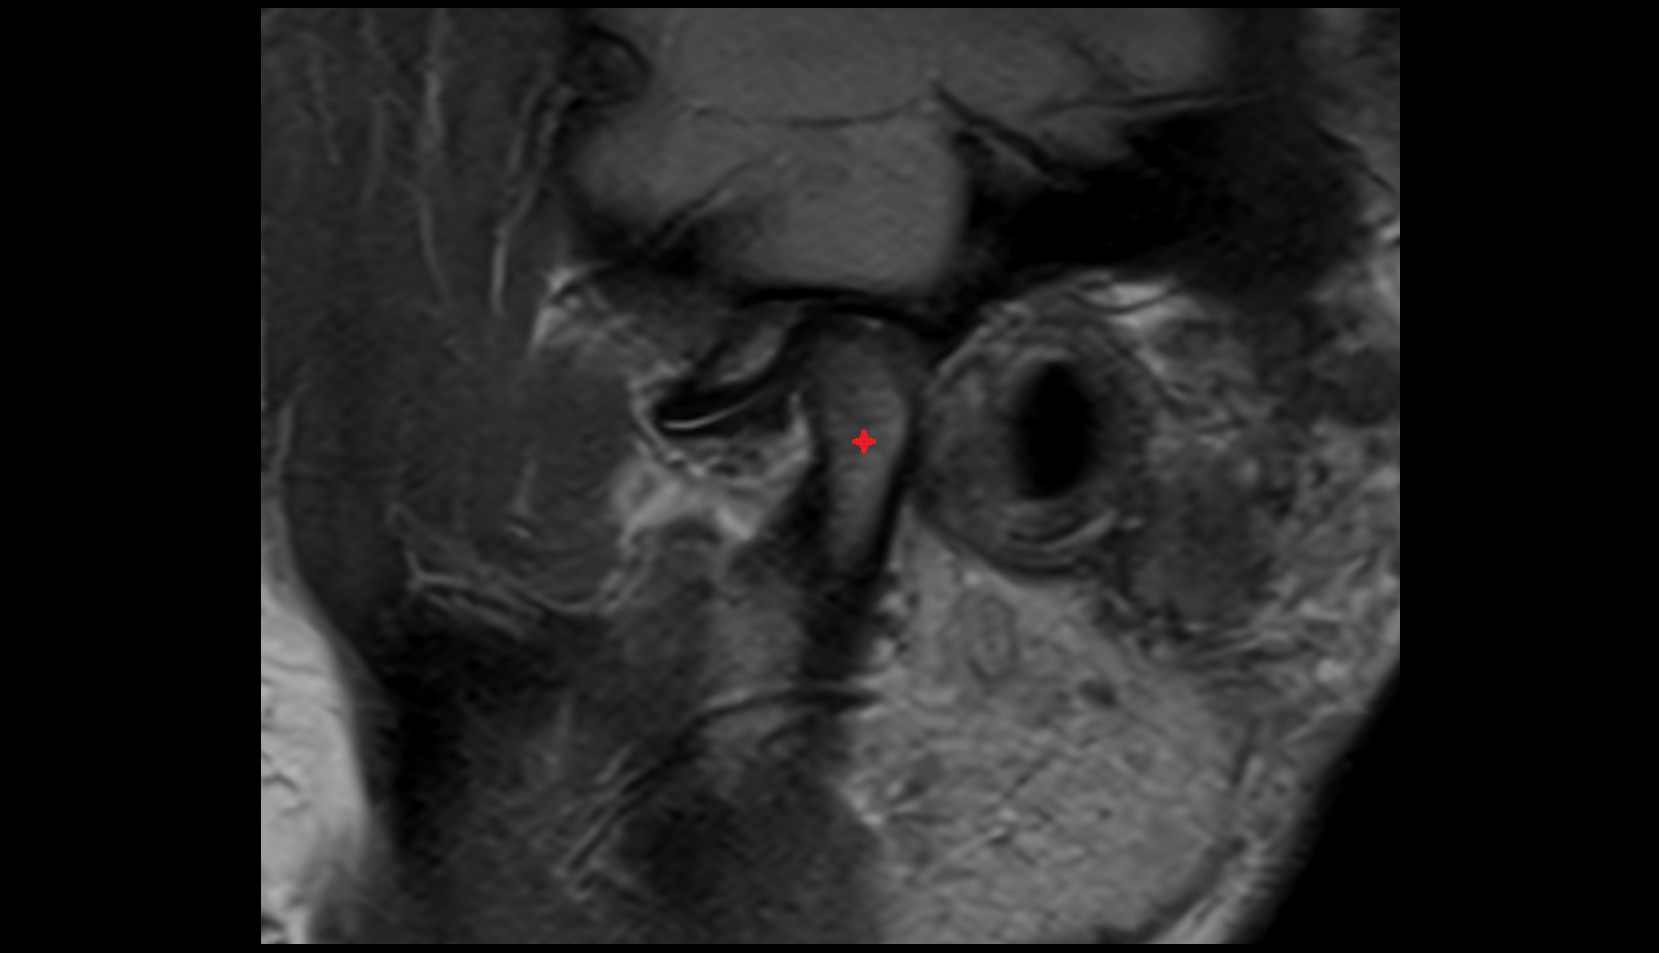

- Articular disc of temporomandibular joint

- Anterior Band of Articular Disc TMJ

- Posterior band of articular disc, TMJ

- Intermediate zone of articular disc

- Superior retrodiscal layer

- Superior synovial membrane of temporomandibular joint

- Temporomandibular joint

- Mandibular condyle

- Mandibular fossa